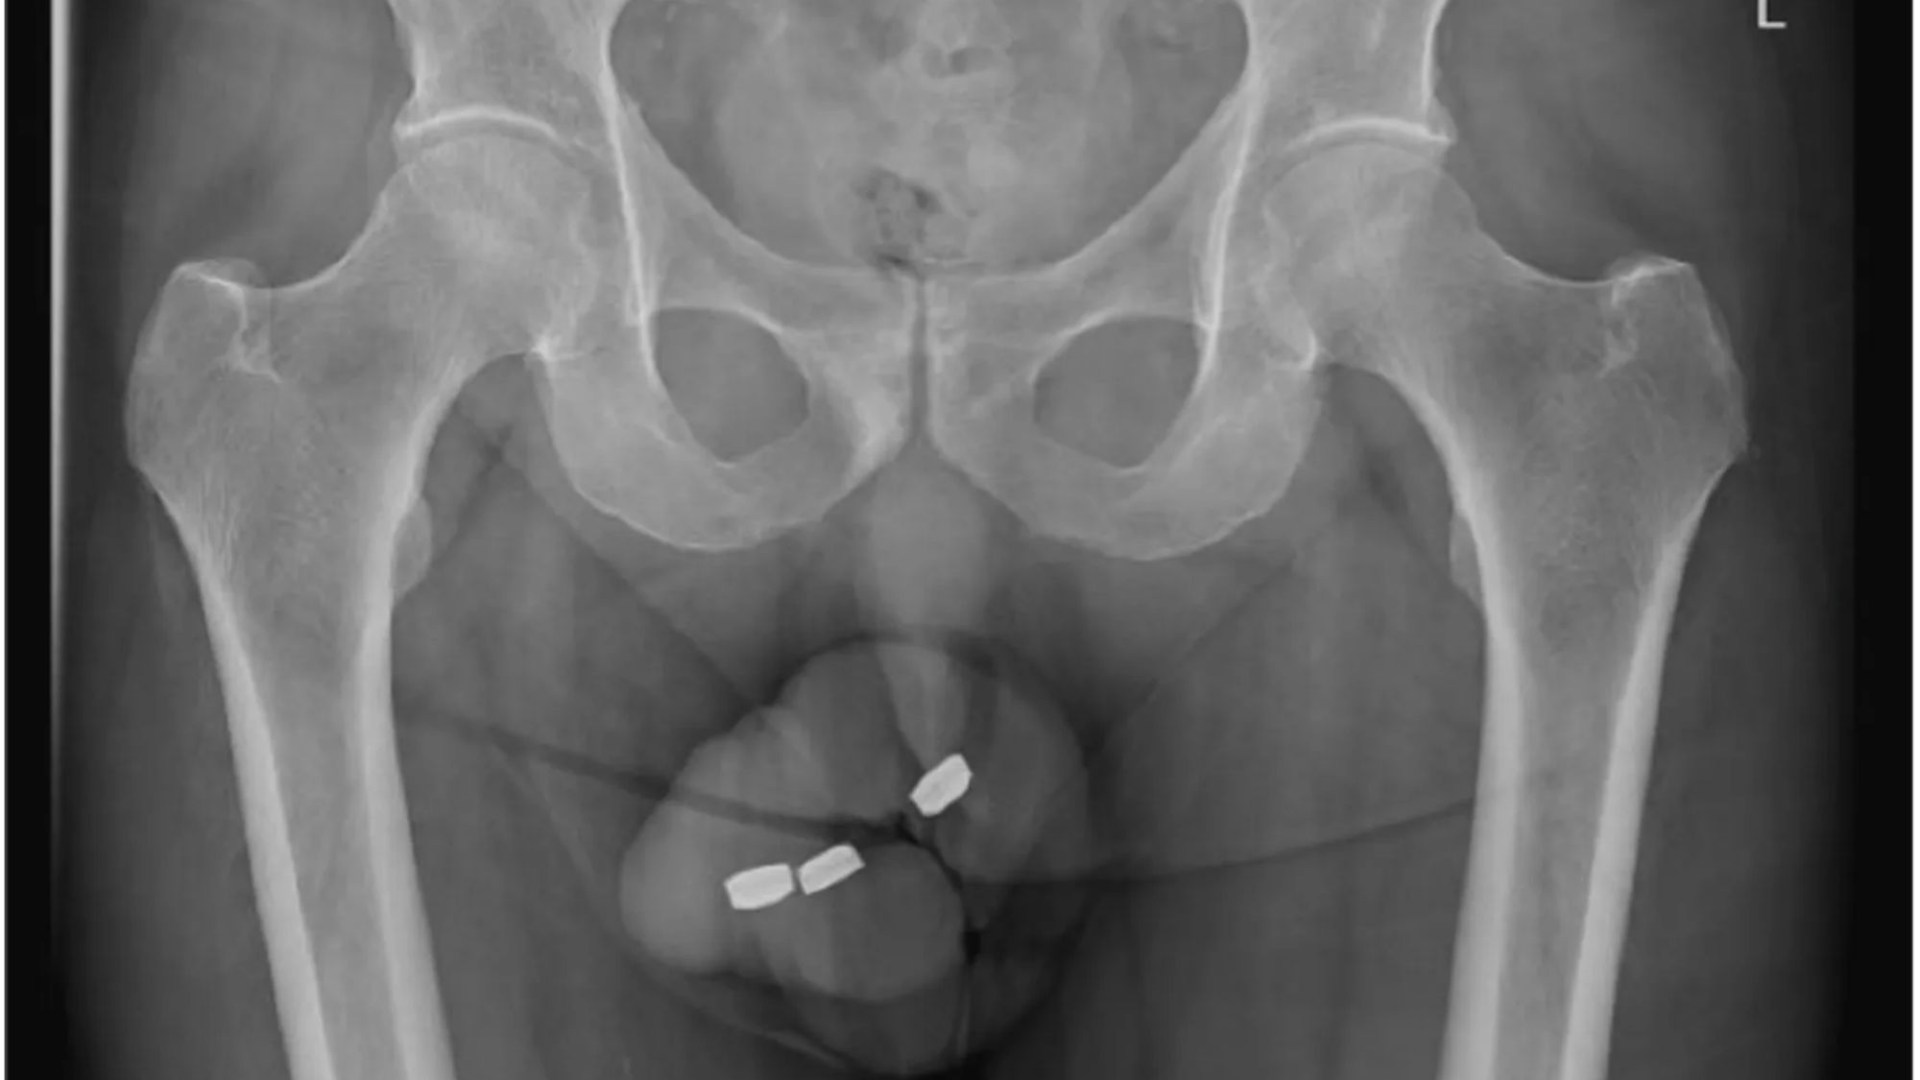

A MAN’S penis rotted from the inside after he shoved three batteries up his urethra, medics have revealed.

The 73-year-old Australian waited a whole day before seeking medical attention because he couldn’t get the 1cm-wide button batteries back out.

He told doctors he had put them in there for “self-gratification purposes” and hadn’t suffered issues with the act in the past.

But after 24 hours, the batteries were starting to cause him “moderate pain”, as well as making his foreskin severely tight and causing issues with peeing.

Dr Brendan Akihiko Yanada, of Western Health in Victoria, said the battery acid had leaked and already caused necrosis — when tissue starts to rot.

In the latest shocking case, reported in Urology Case Reports, doctors found the man’s urethra had been stained black by the batteries.

He was put under general anaesthesia and medics were able to successfully remove them, finding they were coated with a “black tar-like material”.

They operated on the organ again, finding an 8cm section of dead tissue in the shaft that had to be removed.